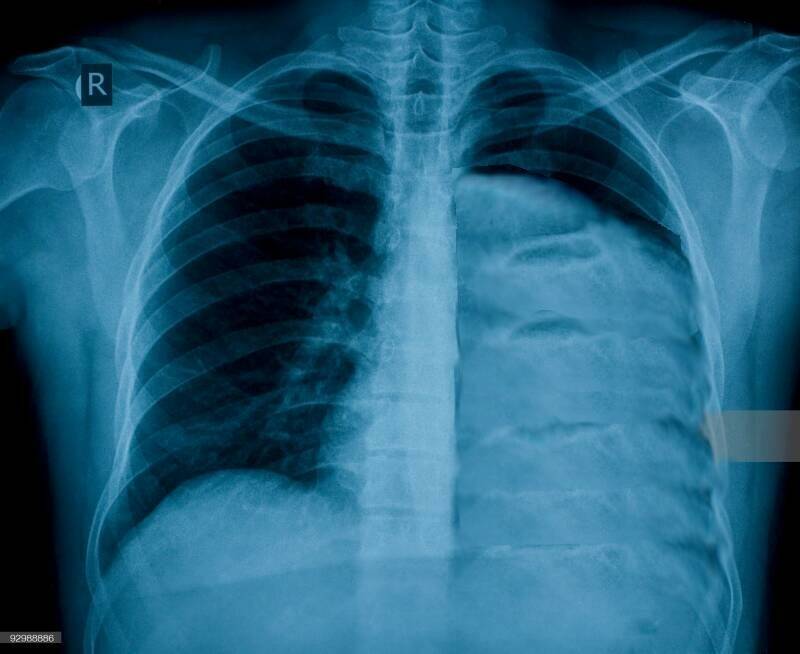

Hier werden foto’s gemaakt en een aantal scans, er werd me gemeld dat ik een aantal tumoren in borst , dikke-darm en prostaat zou hebben.

Waardoor de linker long in elkaar wordt gedrukt, en weinig of niet meer functioneert.

Het bloed wordt nog wel van uit de rechter hartkamer via de linkerlong naar de rechter boezem gepompt , echter hoegenaamd niet van zuurstof voorzien.

Door het bestralen is mijn rechter long van een harde rand voorzien zodat het beperkt is in het ventileren.

Inmiddels lijd ik al maanden aan een hartritme storing en na een longfoto en echo is gebleken dat ik een hoop vocht achter longen heb. Er werd een longpunctie gedaan en wat vocht is op kweek gezet.

8-1-2018 Longfoto’s en long scan vocht achter de long is weg.

2 X door de TC scan geweest , long functie , het is gebleken dat mijn ene long die nog werkt zorgwekkend achteruit is gegaan , het ademen is vaak moeilijk en ook het lopen is moeilijk.